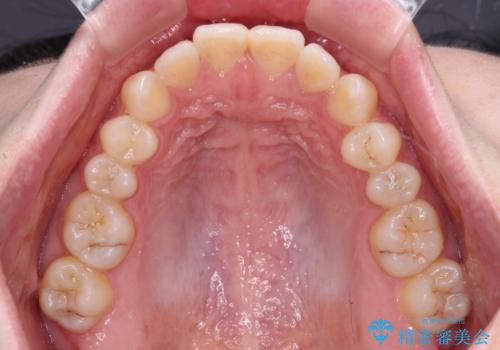

- 前歯の隙間を気にして来院された患者様です。

隙間や叢生の程度はそれほど著しいものではなかったので、インビザラインでもワイヤー矯正でも対応可能でしたが、極力目立たない装置を希望されたため、インビザラインにて矯正治療を行うこととしました。

すきっ歯の原因は色々ありますが、嚥下や発音時の舌突出癖が大きな原因となることがあります。

こちらの患者様も強い突出癖があったため、舌のトレーニング指導を行いました。